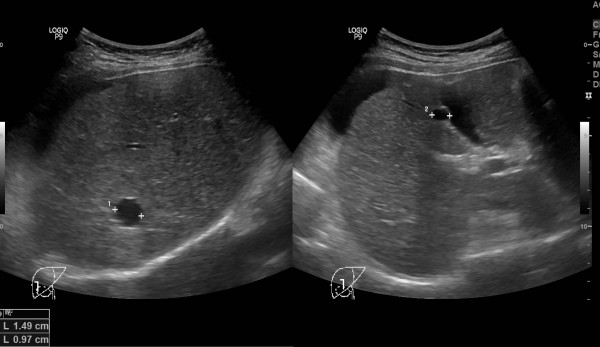

[내막암, 하혈]